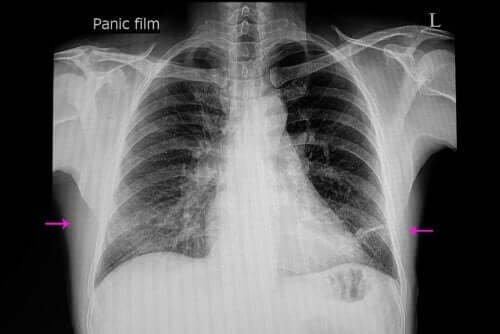

폐확장부전 진단은 적절한 임상 조사와 엑스레이만 있으면 할 수 있다. 한편 의사는 진단을 내리거나 그 심각도를 결정하기 위해 일련의 기술을 사용할 수 있다.

이러한 기술에는 CT 스캔(컴퓨터 단층 촬영), 기관지경 검사, 초음파 및 산소 측정법이 있다. 실제로 기관지경 검사를 통해 폐색을 발견하고 그 막힌 상태를 해결할 수 있다.